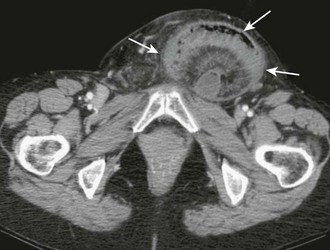

When findings on physical examination are equivocal and the emergency clinician suspects an occult hernia, several options are available for diagnostic imaging.31 Magnetic resonance imaging has a high positive predictive value for patients with clinically uncertain herniations,32 and computed tomography can also be helpful for the diagnosis of hernias and any associated complications (e.g., bowel obstruction or perforation)33 (Figs. 44-6 and 44-7). Ultrasound examination has been shown to have good sensitivity and specificity for the diagnosis of groin hernias34 and may decrease the rate of emergency surgery by improving the ability to reduce hernias.35 Ultrasound may also have good specificity and a high positive predictive value for diagnosing postoperative incisional hernias.31

In rare instances a strangulated or incarcerated hernia may inadvertently be reduced en masse to a preperitoneal location (Fig. 44-8), thus making the hernia sac and contents no longer palpable.36–38 In this case the hernia has not been reduced into the peritoneal cavity and the incarceration and ischemia have not been relieved. Because the clinician believes that the hernia has been appropriately reduced, this can result in delay in the diagnosis of incarcerated or ischemic bowel. Fortunately, this occurs in less than 1% of hernias.39 One case report described a 3-month-old patient whose gangrenous intestines were completely reduced into the peritoneal cavity (not the preperitoneal fat), thereby leading to delayed diagnosis and significant morbidity.40 Persistent pain after reduction of a hernia, especially more than at the orifice of the fascial defect, should alert the physician to the possibility of either properitoneal reduction or reduction of ischemic bowel.